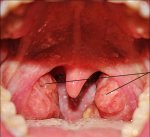

Аденоиды

При лечение аденоидов таблетки неэффективны, капли также неэффективны. Народная медицина советует использовать, для лечения аденоидов, полоскание носа...